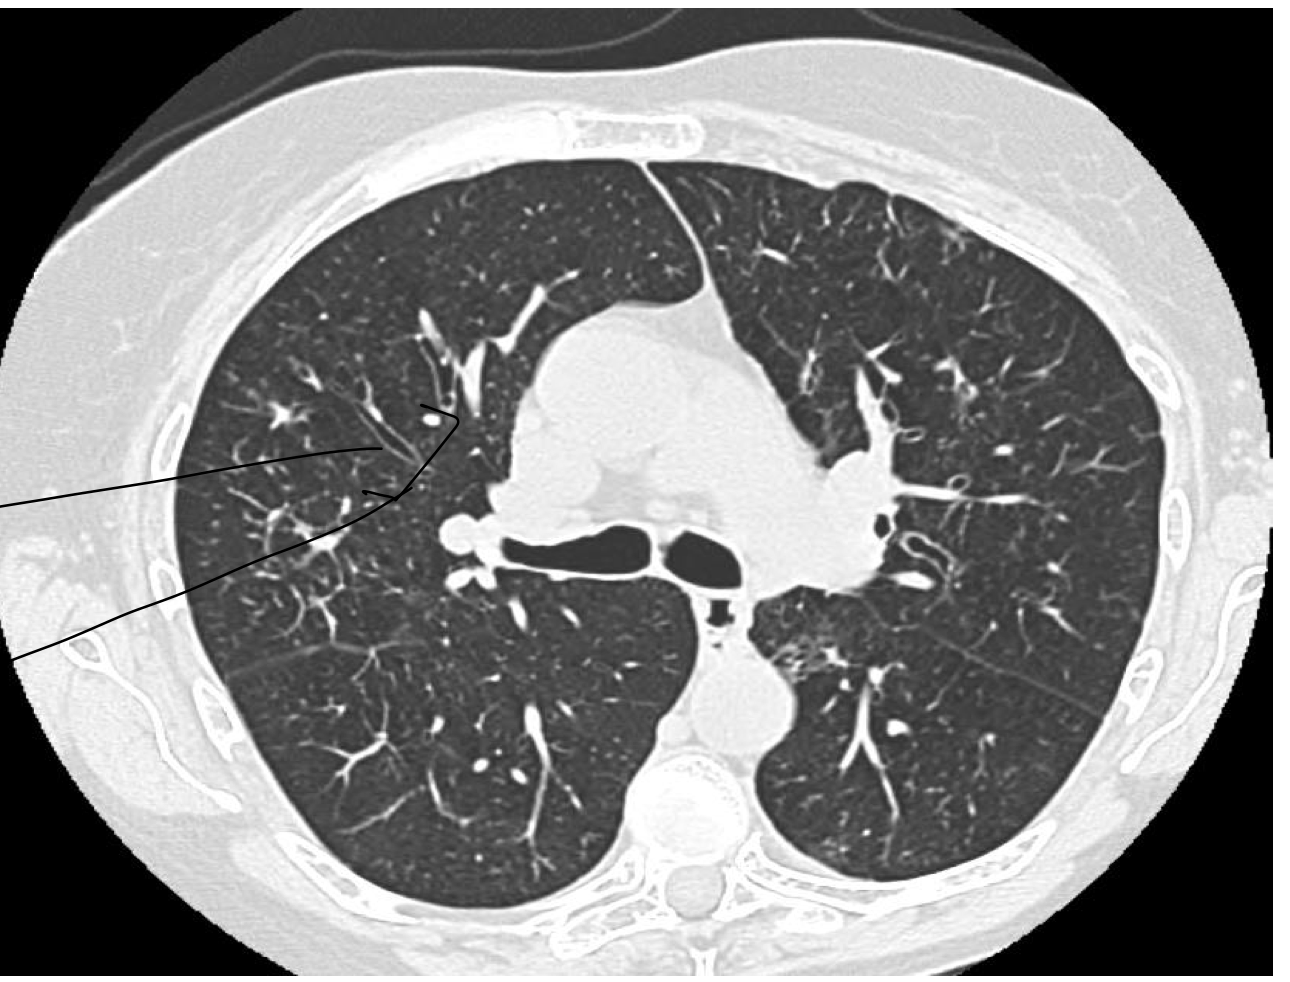

what sign are the arrows

dilated airway indicating TRAM TRACKING– parallel traks. doesn’t taper.